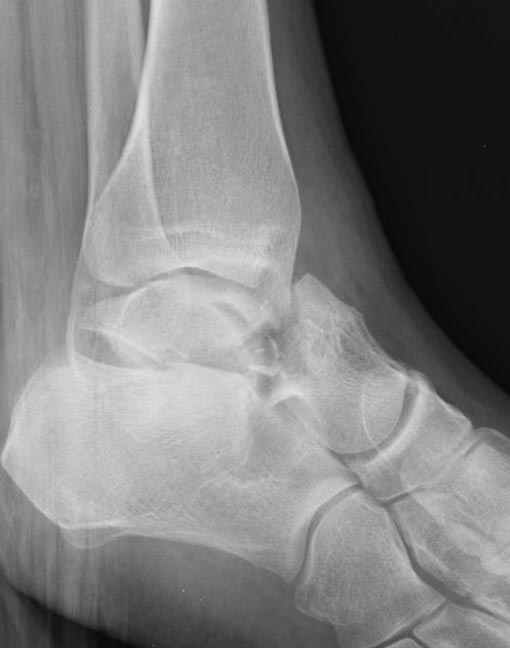

Вдогонку по поводу перелома таранной кости, больная 81, не страдает диабетом, перелом закрытый, в первый же день поступления ограничились временным наружным фиксатором (как на снимке).

За пару недель насчитал 5 больных с переломом таранной кости, из них двое с двусторонним повреждением.

Из-за отека на стопе тактика лечения у всех была

одинаковая: временная наружная фиксация до спадения отека, при изолированных переломах они выписывались домой и через дней 7 госпитализировались на оперативное лечение.

Примеры на снимке...